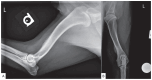

Prototheca osteomyelitis in a dog

Canine systemic protothecosis is an uncommon disease caused by Prototheca spp., which are saprophytic algae occurring ubiquitously in nature. Infection occurs most commonly in immunocompromised animals. Most infected dogs have chronic large-bowel diarrhea, ocular lesions, neurologic deficits, or a combination thereof, but various tissues can be affected. This case highlights a unique presentation of protothecosis in a dog, in which lameness resulting from osteomyelitis was the predominant clinical sign. Key clinical message: Although osteomyelitis is an atypical manifestation, protothecosis can be a differential diagnosis for an aggressive bony lesion and is particularly worthy of consideration in immunocompromised dogs.